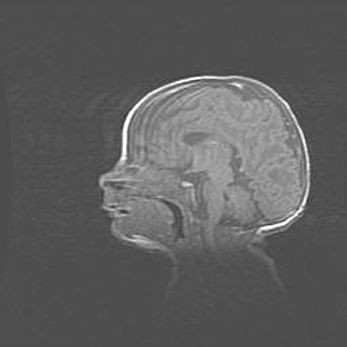

Аномалия Денди-Уокера. Признаки гипоплазии мозолистого тела.

Возраст: 5 месяцев 3 дня

Вес: 5550 г

Пол: мужской

Окружность головы: 39 см

Срок гестации: 40 недель

Аномалия Денди-Уокера – это порок развития головного мозга, для которого характерна триада симптомов: гипотрофия или аплазия червя мозжечка и/или полушарий мозжечка, расширение четвёртого желудочка с формированием ликворной кисты задней черепной ямки, гипертензионная гидроцефалия различной степени.

Гипоплазия мозолистого тела относится к дефектам внутриутробного этапа развития мозговой ткани, возникающим в процессе закладки структур головного мозга, что происходит на начальных этапах развития эмбриона.